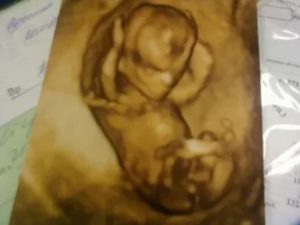

УЗИ на тринадцатой недели развития плода необходимо. Ведь, если у малыша есть какие-то отклонения или патологии, то, выявив их, можно потерять драгоценное время. УЗИ хорошо показывает развитость внутренних органов малыша. При УЗИ плода на тринадцатой недели можно увидеть, как малыш сосет свой пальчик.

Можно также увидеть, как грудная клетка совершает движения, так она готовит ребенка к его первому вдоху. При УЗИ на этом этапе беременности измеряют поперечный размер и окружность живота. Если полученные данные превышают норму в полтора раза, то их можно считать неблагоприятными.

УЗИ на 13 неделе беременности

Поскольку период проведения первого планового УЗИ охватывает промежуток между 10 и 14 неделей, возможно, что оптимальным вариантом для проведения исследования врач определит именно какой-либо из дней 13 недели.

УЗИ на 13 неделе беременности уже четко покажет очертания малыша, расскажет о его размерах, отобразит, как кроха двигается, сгибает и разгибает ручки-ножки. При проведении ультразвукового исследования врач также сможет оценить состояние матки, место крепления и предлежание плаценты, установить приблизительный срок предстоящих родов.

Необходимо УЗИ еще и для выявления возможных пороков развития плода на ранних сроках беременности или тяжелых врожденных аномалий. Вот только необходимо помнить: результаты ультразвукового исследования ни в коем случае не могут трактоваться как окончательный диагноз. Это – всего лишь повод для проведения углубленного расширенного обследования и, возможно, консультации у генетика.

Так как время проведения первого планового ультразвукового исследования беременности захватывает период между десятой и четырнадцатой неделей, то велика вероятность, что наиболее лучшим временем для выполнения ультразвукового исследования ваш лечащий врач назначит на непременно какой-нибудь из дней тринадцатой недели. Ультразвуковое исследование на этом сроке позволит четко увидеть очертания ребеночка, опишет его размеры. Можно будет увидеть движение плода, как он может сгибать и разгибать ручки с ножками. Во время проведения УЗИ специалист имеет возможность оценить состояние матки, где крепится и предлежит плацента, также может поставить вероятный срок предстоящих родов.Функцией такого УЗИ в том числе является выявление вероятных отклонений в развитии малыша на раннем сроке либо серьезных врожденных аномалий. Результаты исследования плода не являются окончательным диагнозом,а только поводом для проведения более углубленного детального обследования.